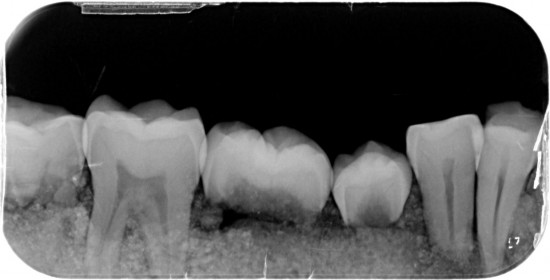

Linker helft 3 molaren ,1 premulaar , 1 gebroken premulaar ,1 hoektand , 3 snijtanden .

Rechter helft 3 molaren , 2 premularen , 1 hoektand, 2 snijtanden .

Totaal 5 snijtanden ?

Dit kaakje werd door mijn tandarts grondig bekeken en róntgen foto,s van gemaakt .

Met zijn  langdurige ervaring  uit zijn eigen praktijk. Kunnen namelijk  Molaren verkeerd om zitten. (zie 1ste  molaar linker kaak)

Tevens kunnen er zowel  tanden teveel of te weinig voorkomen .( zie 5 snijtanden ) . De 5de premulaar en hoektand lijken maar een  tand  te zijn , zie rechterkaak. Rontgenfoto wijst echter uit dat het toch 2 aparte tanden zijn .